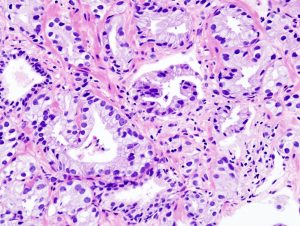

Chance auf Langzeitüberleben beim fortgeschrittenen Nierenzellkarzinom

Informieren Sie sich über Nivolumab + Ipilimumab als Erstlinientherapie bei Patient:innen mit fortgeschrittenem Nierenzellkarzinom.